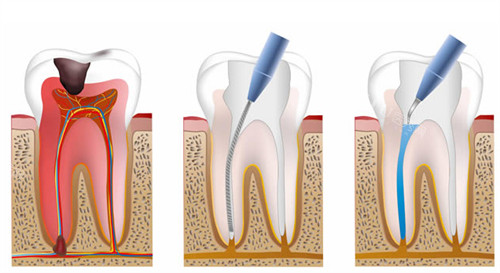

根管治疗

对于牙髓炎和根尖周炎等引起的牙痛和下颚疼痛,根管治疗是一种有效的治疗方法。

根管治疗通过清除受感染的牙髓组织,填充根管并封闭冠部,从而消除炎症、降低疼痛。根管治疗后,牙齿可能会变得脆弱,需要佩戴牙冠进行保护。